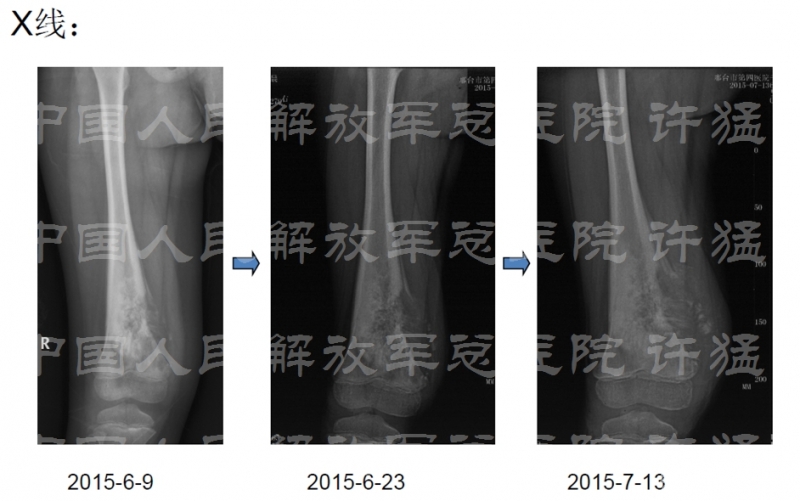

治疗及化疗后影像学检查: